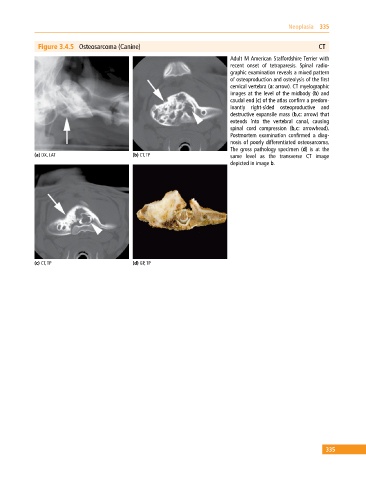

Figure 3.4.5 Osteosarcoma (Canine) CT

Adult M American Staffordshire Terrier with

recent onset of tetraparesis. Spinal radio

graphic examination reveals a mixed pattern

of osteoproduction and osteolysis of the first

cervical vertebra (a: arrow). CT myelographic

images at the level of the midbody (b) and

caudal end (c) of the atlas confirm a predo m

inantly right‐sided osteoproductive and

destructive expansile mass (b,c: arrow) that

extends into the vertebral canal, causing

spinal cord compression (b,c: arrowhead).

Postmortem examination confirmed a diag

nosis of poorly differentiated osteosarcoma.

The gross pathology specimen (d) is at the

(a) DX, LAT (b) CT, TP same level as the transverse CT image

depicted in image b.